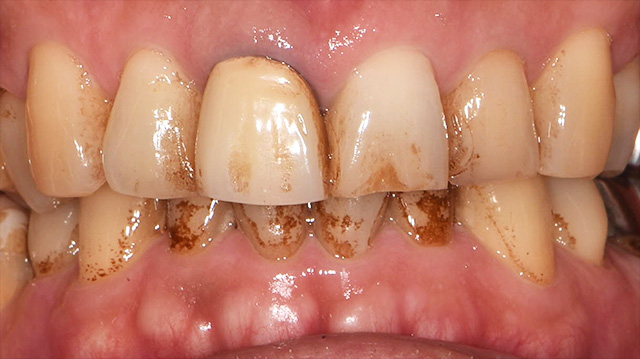

| 年代・性別 | 50代 男性 |

|---|---|

| 主訴 | 転倒して歯が割れた |

| 治療回数 | 3回 |

| 治療期間 | 約1ヶ月 |

| 費用 | 仮歯 5,500円 ジルコニアクラウン 176,000円 |

*キャンセルポリシーをご一読のうえご予約ください